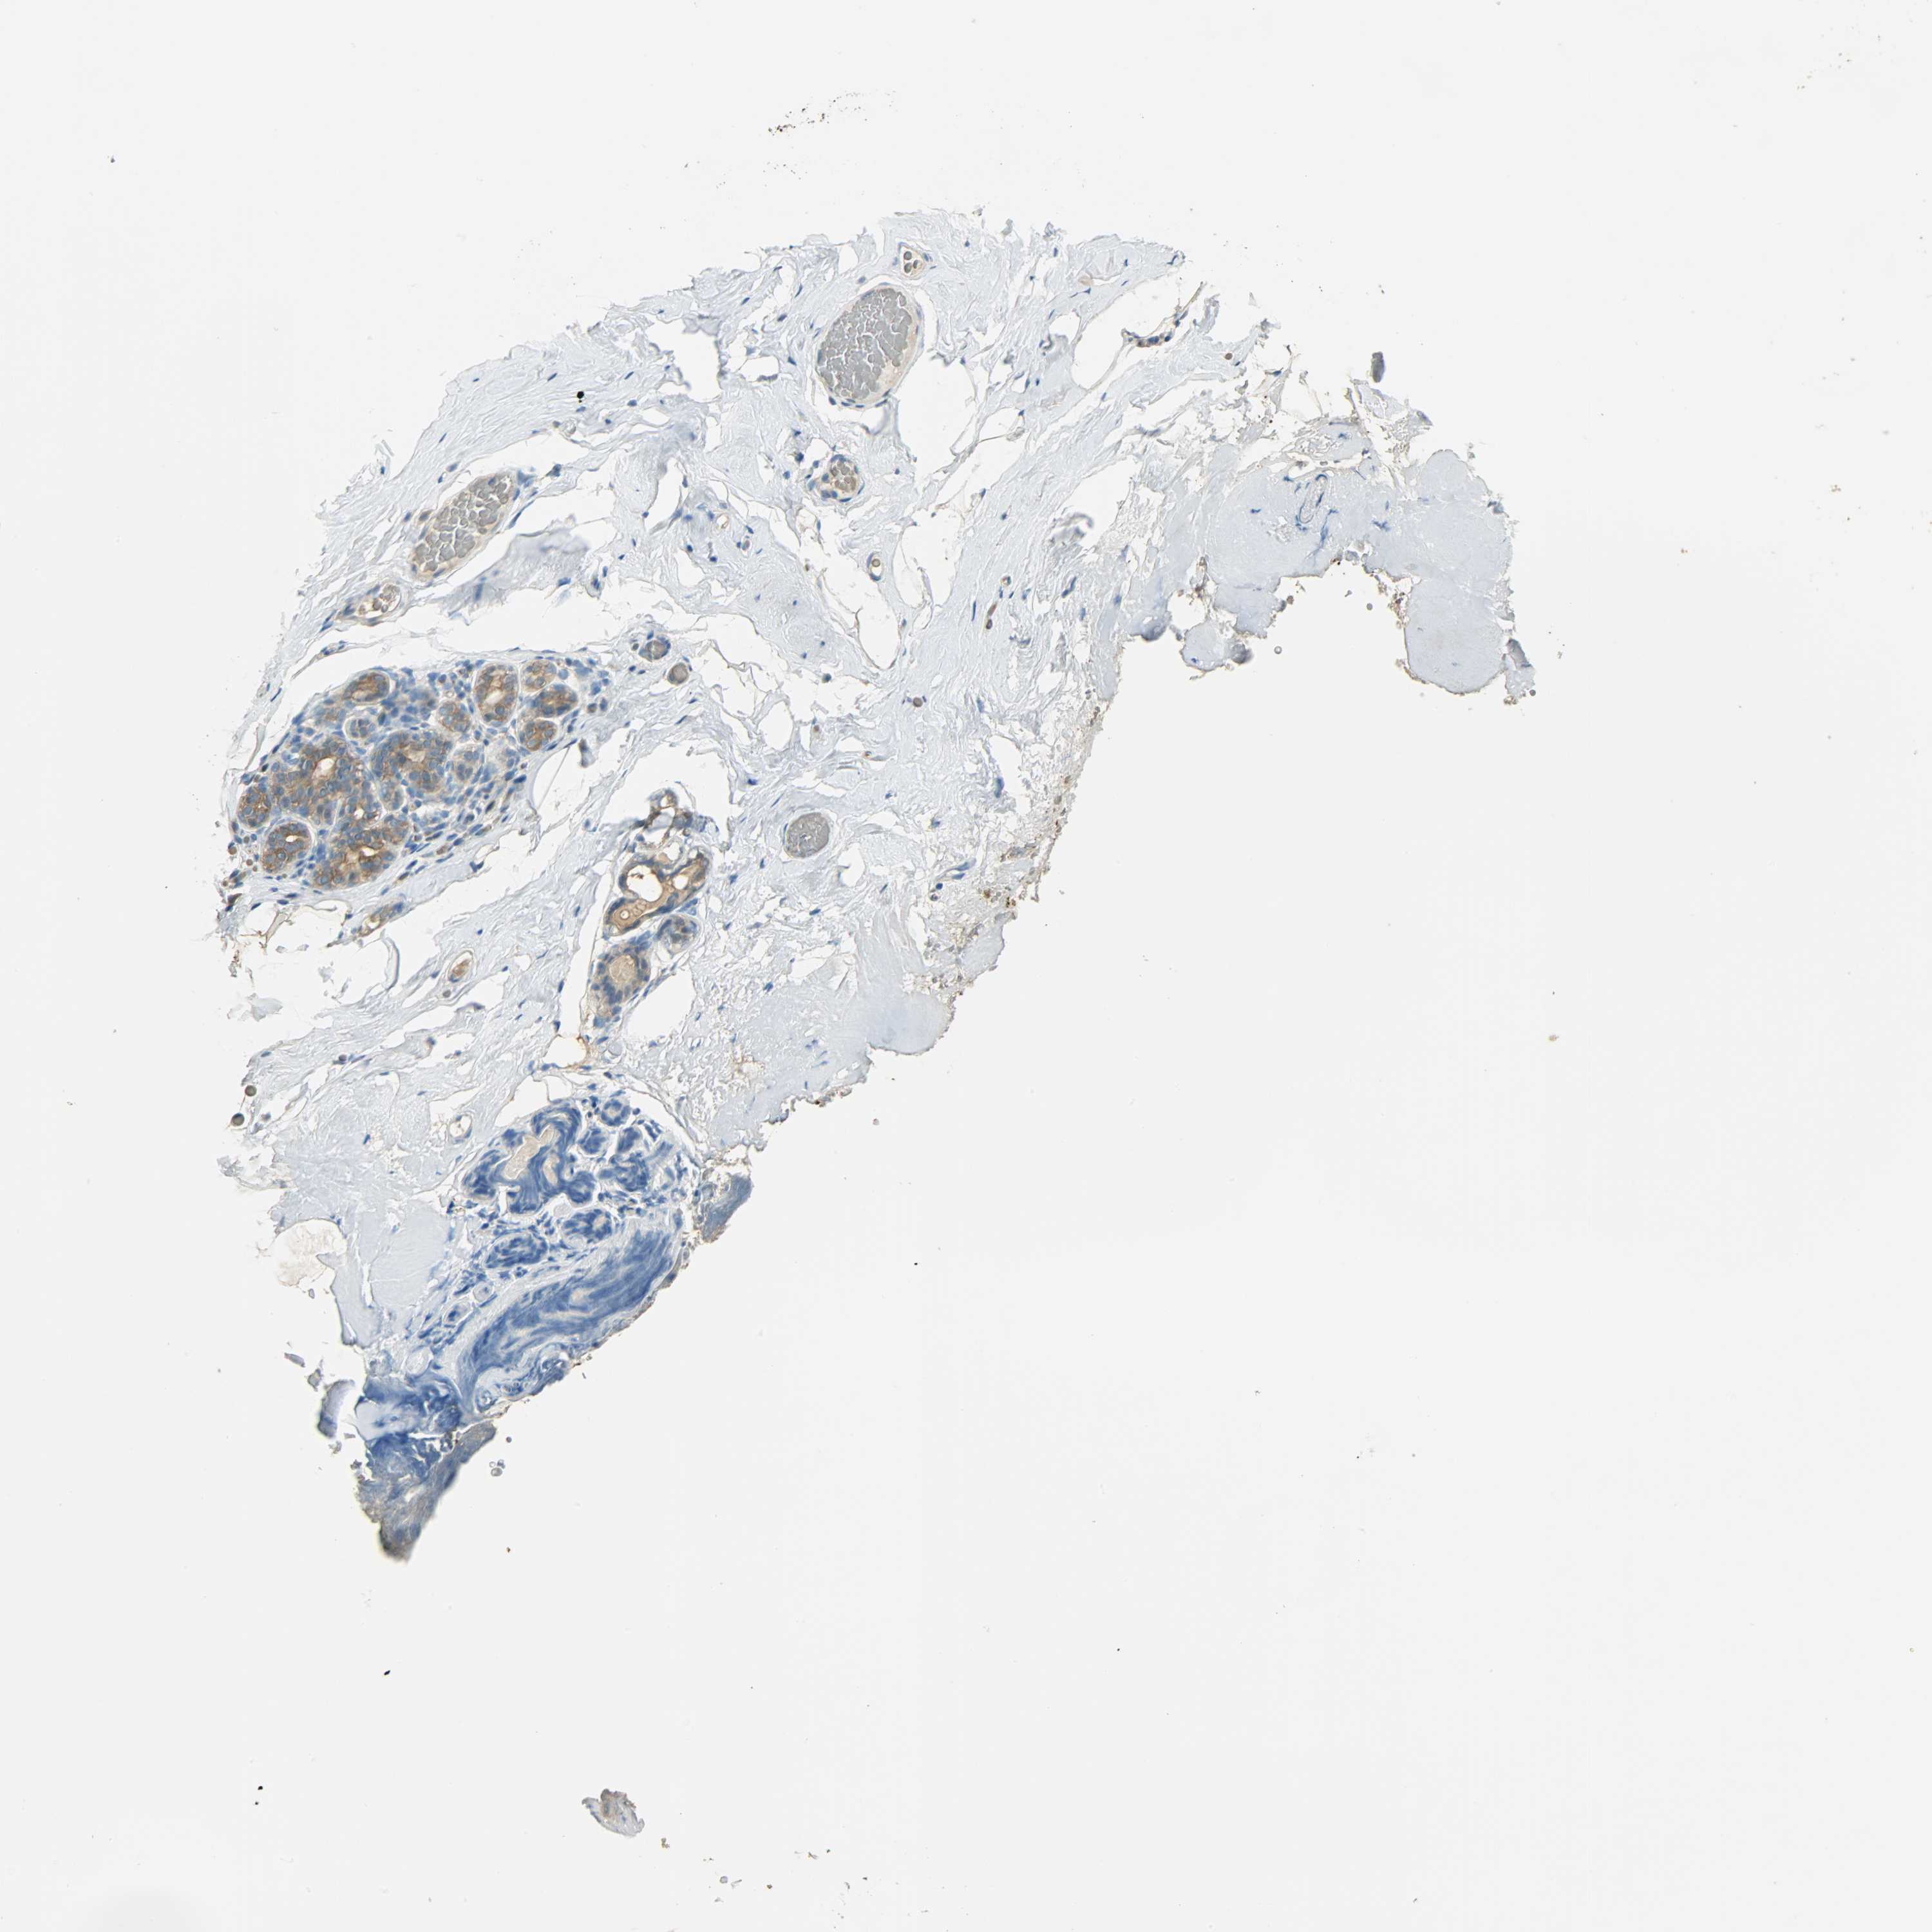

Antibody staining in the annotated cell types in the current human tissue is reported as not detected, low, medium, or high. This score is based on the staining intensity and fraction of stained cells.

Information about each individual sample is listed below, including gender, age, a tissue section image and estimated fractions of cell types. pTPM (transcripts per million) values give a quantification of the gene abundance which is comparable between different genes and samples.

Glandular cells: 15 Adipocytes: 5 Other cell types: 80

Female, age 80

Breast sample 390 pTPM: 35.3

Cell types%